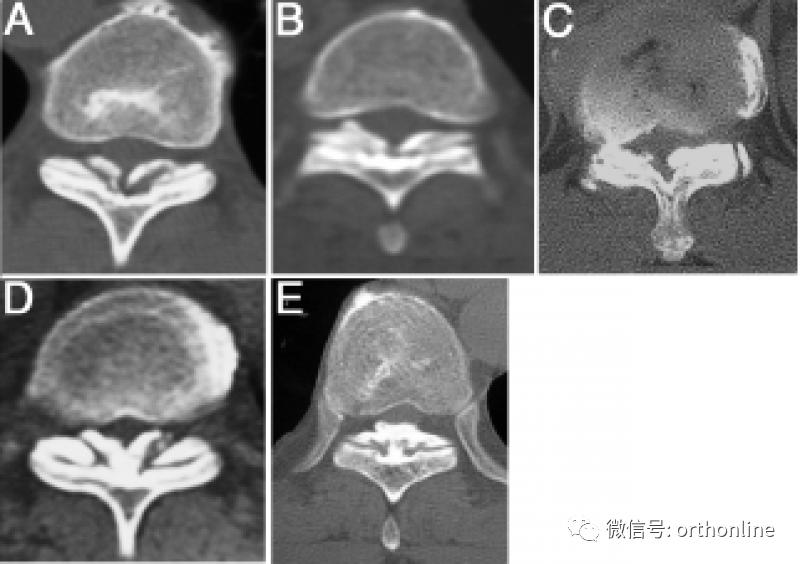

1.CT分型:按照轴位CT分为外侧型、延展型、肥厚型、融合型、结节型。

A.外侧型(Lateral type):黄韧带囊部骨化,骨化物位于椎管外侧缘;

B.延展型(Extended type):椎板间部黄韧带骨化;

C.肥厚型(Enlarged type):黄韧带骨化侵及椎管内,但中线未融合;

D.融合型(Fused type):双侧黄韧带骨化融合于椎管中线,但中线尚可见凹型切面;

E.结节型(Tuberous type):双侧黄韧带骨化融合并形成骨化结节凸向椎管内。

A.B.圆弧形(Round type);C.D.鸟嘴型(Beak type)